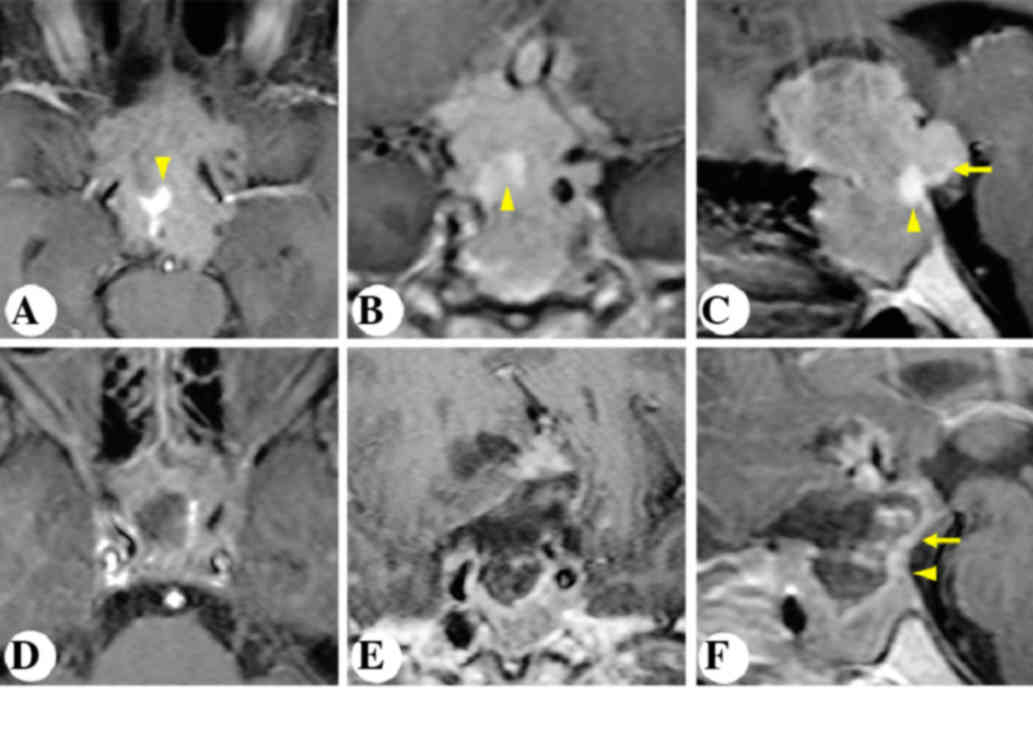

A 63-year-old male complained of severe intermittent headache for the past three years. MRI revealed an intrasellar non-enhancing lesion (Fig. 1). The pituitary gland and stalk was stretched and displaced posterolaterally to the right (Fig. 1A-C). The patient underwent microscopic transphenoidal surgery (Fig. 2). Postoperative MRI demonstrated gross-total resection of the tumor and an anatomically intact gland and stalk (Fig. 1D-F). An intraoperative view of the pituitary gland (Fig. 2) is shown in Fig. 2A after tumor removal.

Figure 1.

Patient 1. Representative post contrast T1-weighted images. Preoperative (A) horizontal, (B) coronal and (C) sagittal MRI images demonstrated the space-occupying lesion in the sellar region. Postoperative (D) horizontal, (E) coronal and (F) sagittal MRI images showed gross-total resection of the tumor and the anatomically intact pituitary stalk and gland. Arrows indicate the pituitary stalk. Arrowheads indicate the pituitary gland. MRI, magnetic resonance imaging.